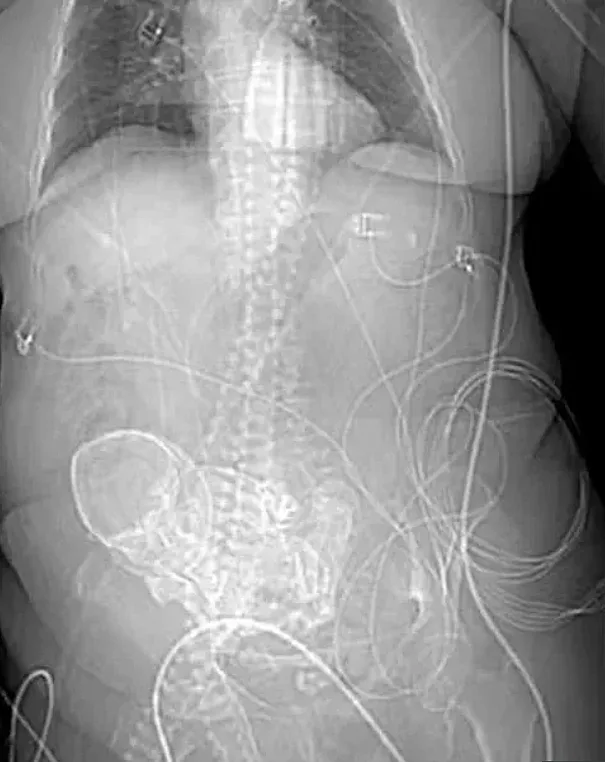

בבדיקה ראשונית שערכו הרופאים, מלבד דלקת בדרכי השתן, לא נמצא דבר חריג, אך למחרת היא פונתה לטיפול נוסף בבית החולים האזורי פונטה פורה. לאחר שעברה צילומים הופתעו הרופאים לגלות כי בתוך רחמה יש עובר מת אותו היא נשאה במשך 56 שנים.

מדובר בתופעה לוואי נדירה של היריון חוץ קדמי הנקראת ליתופדיון (Lithopedion). התופעה מתרחשת כאשר העובר מת במהלך ההיריון והגוף אינו מסוגל לסלק את שרידי העובר. העובר נשאר בחלל הבטן כאשר מעטפת סידן נוצרת מעליו.